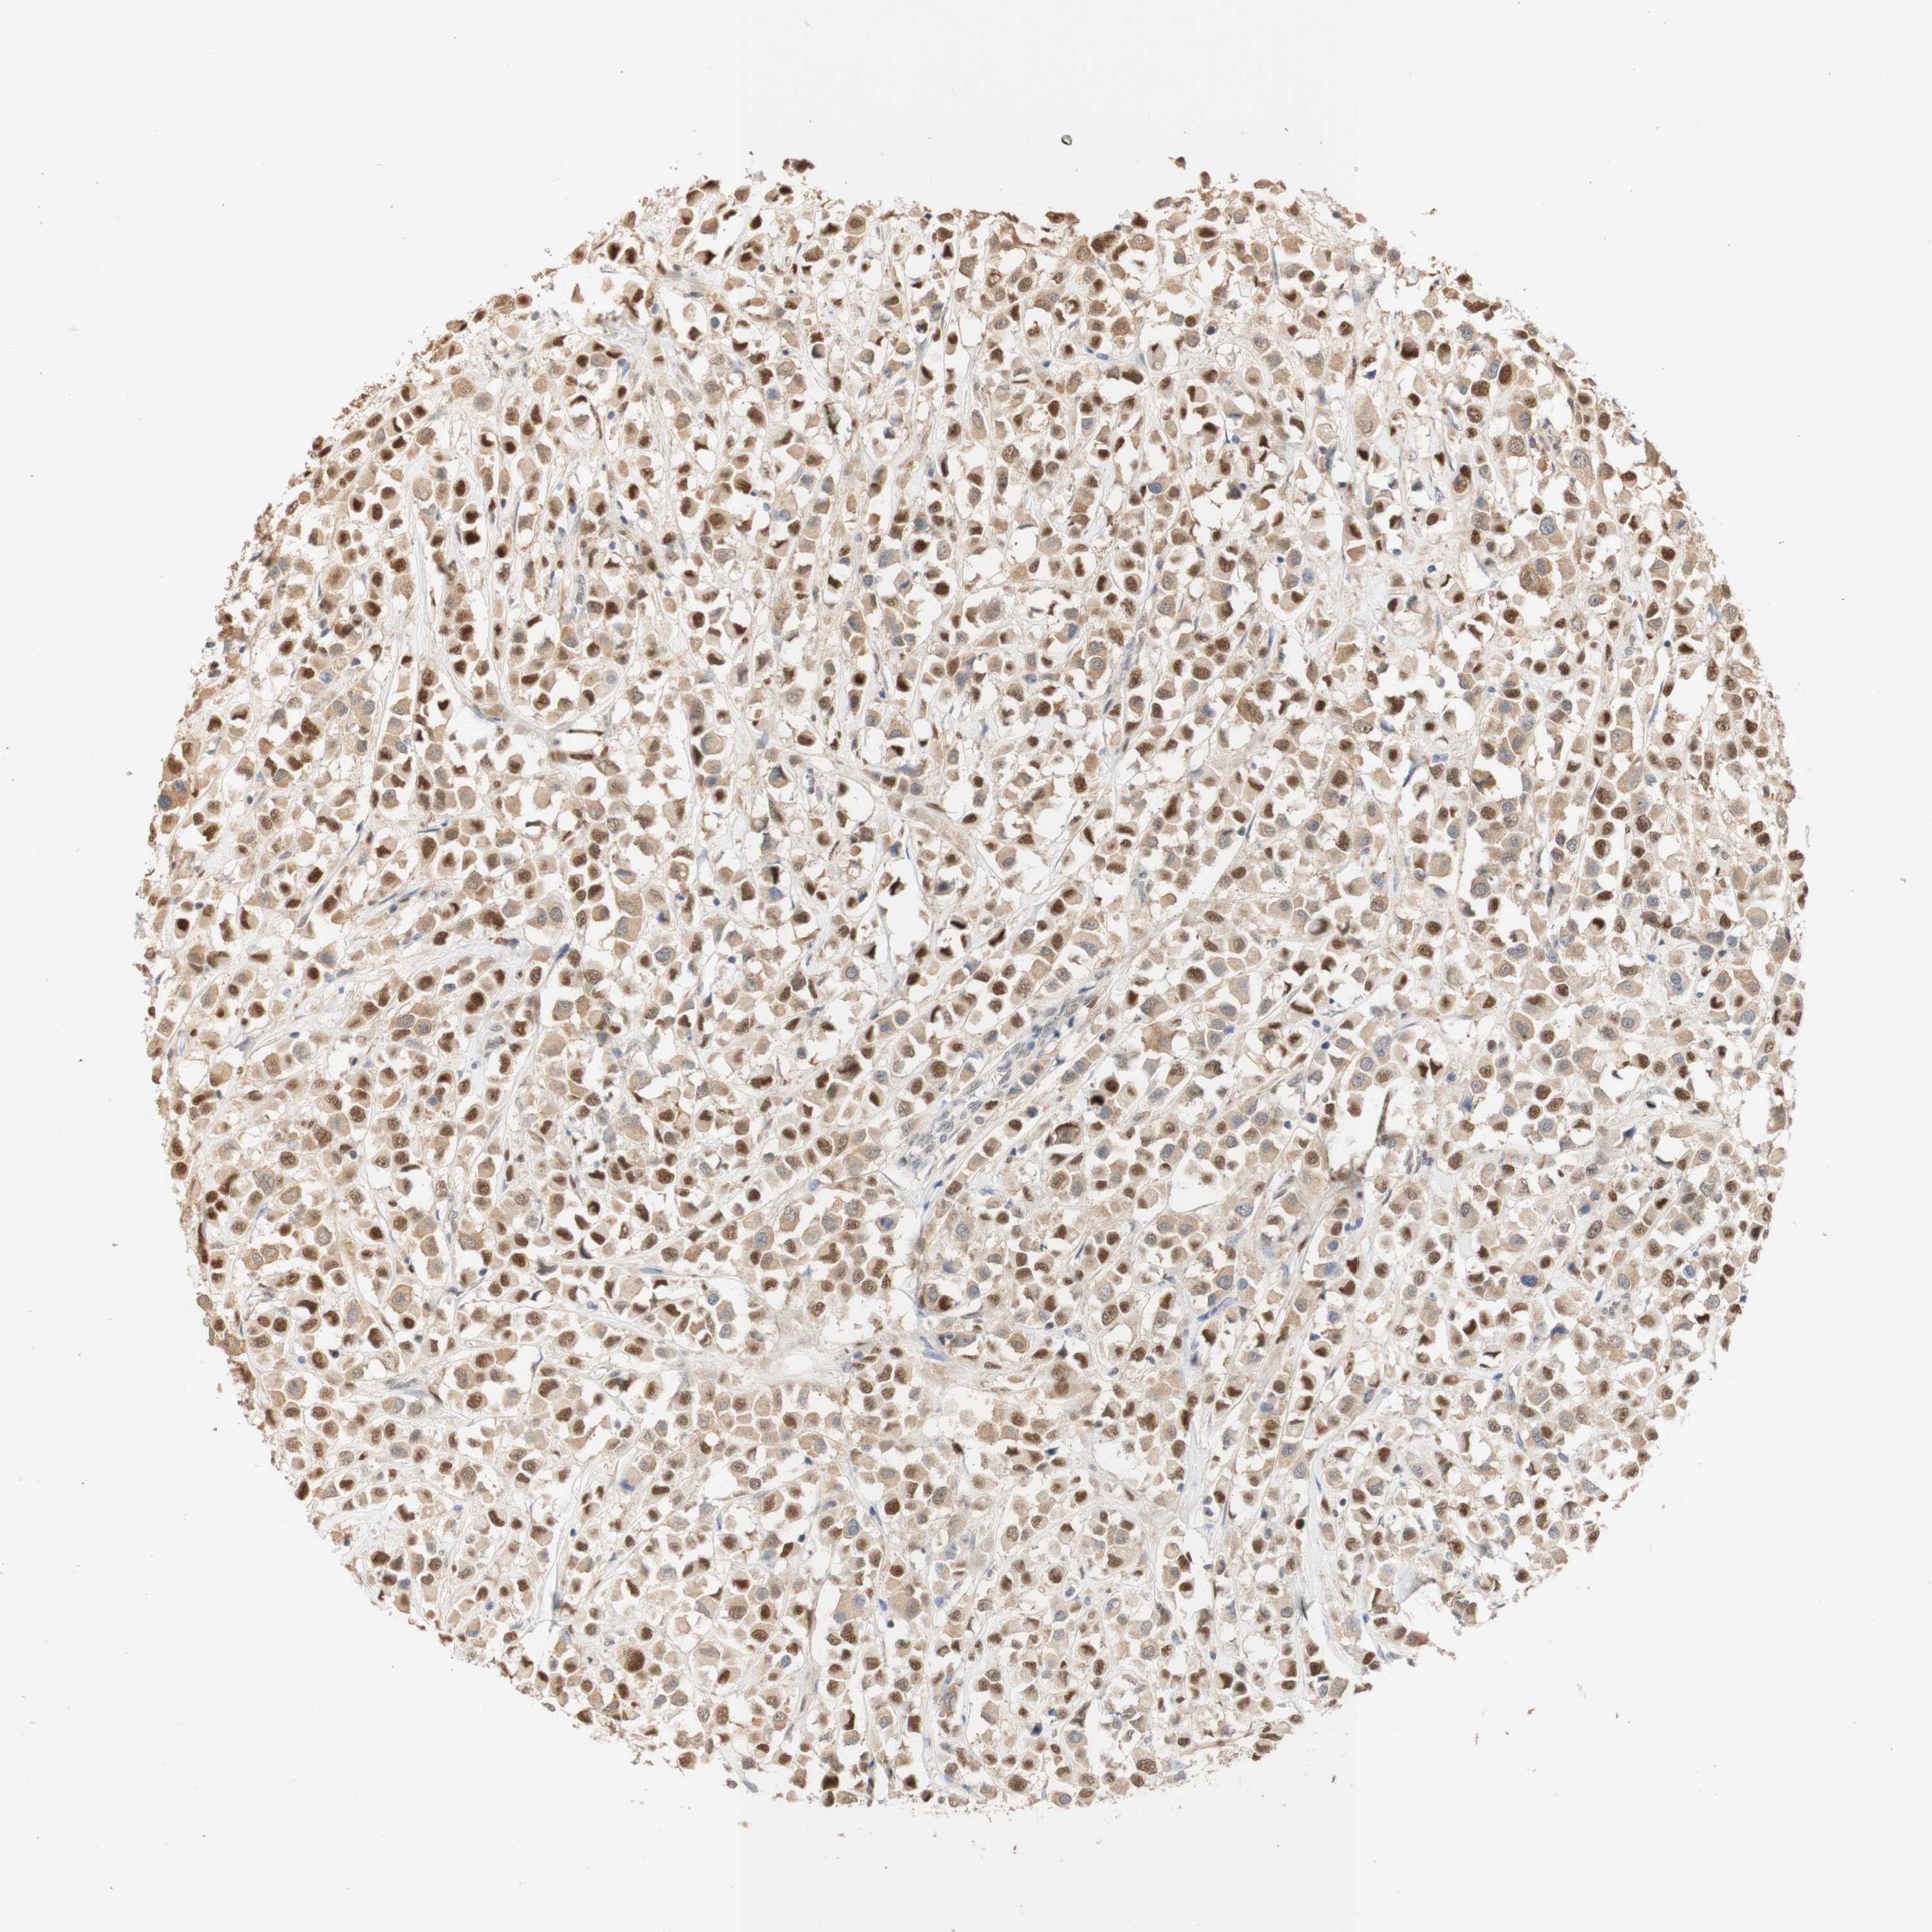

CANCER BREAST CANCER Show tissue menu

BRCA TCGA BRCA VALIDATION PROTEIN EXPRESSION

Breast cancer

Human cancer

Breast invasive carcinoma

MAP3K4 is not prognostic in Breast Invasive Carcinoma (TCGA)